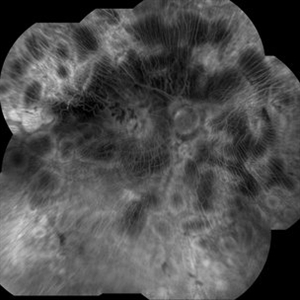

Stargardt's Disease

Stargardt's Disease

Oct 23 2024 by Virginia Gebhart

62 year old female with bullseye RPE changes and flecks, mottled FAF, and silent choroid on FA consistent with late onset Stargardt's Disease. Pt is asymptomatic with 20/20 vision OU at this time

Photographer: Virginia Gebhart, Retina Consultants of Carolina

Imaging device: Optos California

Condition/keywords: Stargardt disease, Stargardts Disease